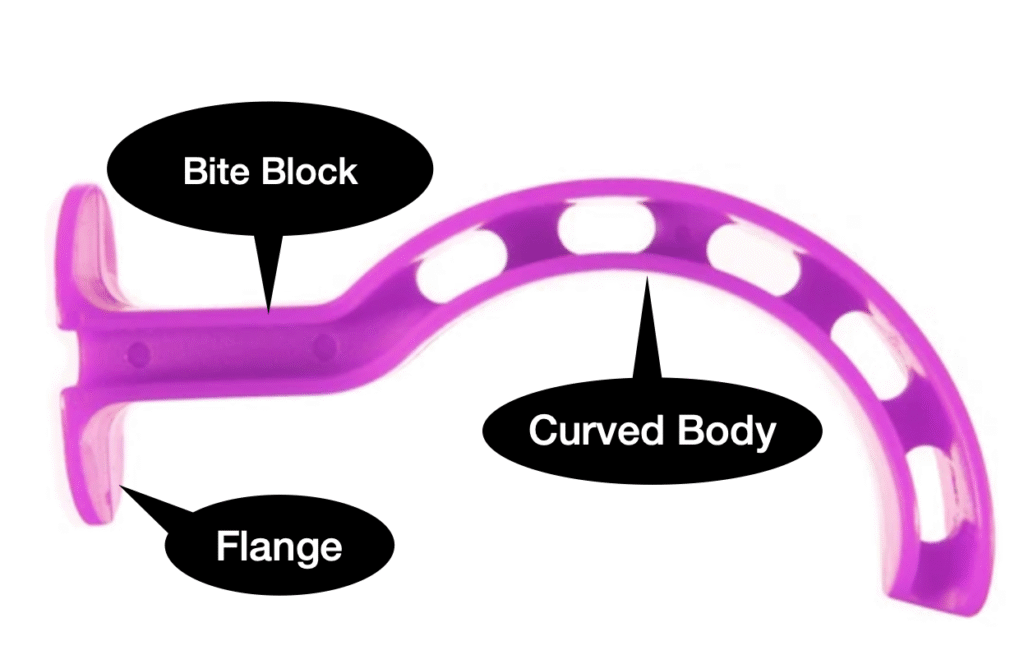

Oral pharyngeal Airway-

| Aspect | Oral Pharyngeal Airway (OPA) in PALS |

|---|---|

| Purpose | Maintain airway patency for unconscious patients |

| Indications | Unconscious patients requiring airway support |

| Insertion Technique |

1. Measure from the corner of the mouth to the angle of the jaw 2. Choose the appropriate size 3. Insert while using a tongue depressor to hold the tongue on the floor of the mouth 4. Insert the OPA with the curve facing the hard palate 5. Rotate 180 degrees to follow the natural curvature of the mouth 6. Ensure flange rests against the lips to prevent deep insertion 7. Secure in place and monitor for discomfort or complications |

| Contraindications | Presence of a strong gag reflex |

| Complications | Gagging or vomiting during insertion |

| Notes |

Regular assessment and monitoring are essential It is still necessary to keep the head and neck in the sniffing position after the oral pharyngeal airway is in place Do not suction for more than 10 seconds at a time Reposition or remove if the patient regains consciousness or complications arise |

| Removal | Remove if the patient regains consciousness and can maintain a clear airway independently |